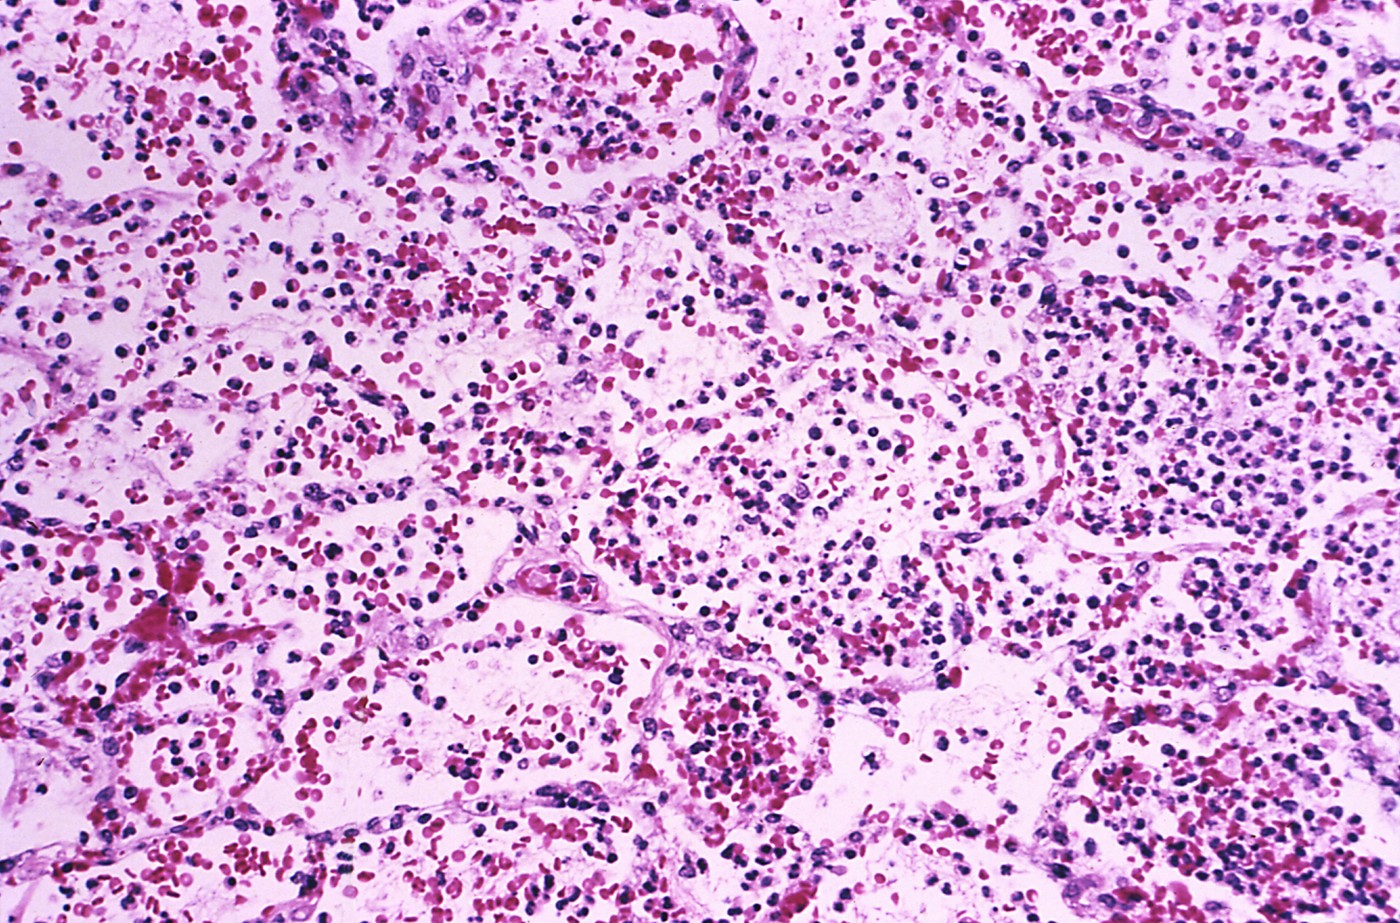

Obstajajo tri pojavne oblike bolezni, pojavi se najkasneje 8 dni po okužbi. Pri najpogostejši obliki, bubonski kugi, bolezenski znaki nastopijo hitro, okuženi nenadoma dobijo visoko vročino, začne jih mraziti, postanejo splošno šibki. V nekaj urah sledi pojav izjemno povečanih in bolečih področnih bezgavk, najpogosteje v pazduhah, dimljah ali na vratu. Če je ne zdravimo, je smrtnost od 30- do 60- odstotna.

Pri septični kugi se bolniku strjuje kri znotraj žile. Nastopi tromboza, s posledično zamašitvijo manjših žil lahko nastane tudi gangrena, zaradi katere je treba opraviti amputacije. Pri majhnem odstotku obolelih se pojavlja meningitis. Še eden izmed simptomov je krvavenje v kožo in krvavitev pljuč. Septična kuga brez zdravljenja skoraj vedno vodi v smrt.

Najredkejša oblika kuge je pljučna oblika, a je najbolj nalezljiva. Lahko se razvije iz nezdravljene bubonske kuge ali se prenaša kapljično – zato za prenos s človeka na človeka ne potrebuje 'živalskega posrednika'. Začetni znaki so podobni kot pri drugih hudih okužbah dihal, kasneje se pojavi še izkašljevanje krvi. Smrtnost brez zdravljenja je skoraj 100-odstotna. Zadnji večji izbruh pljučne oblike kuge se je zgodil leta 2017 na Madagaskarju, ko se je okužilo 2.348 ljudi, 202 sta umrla.